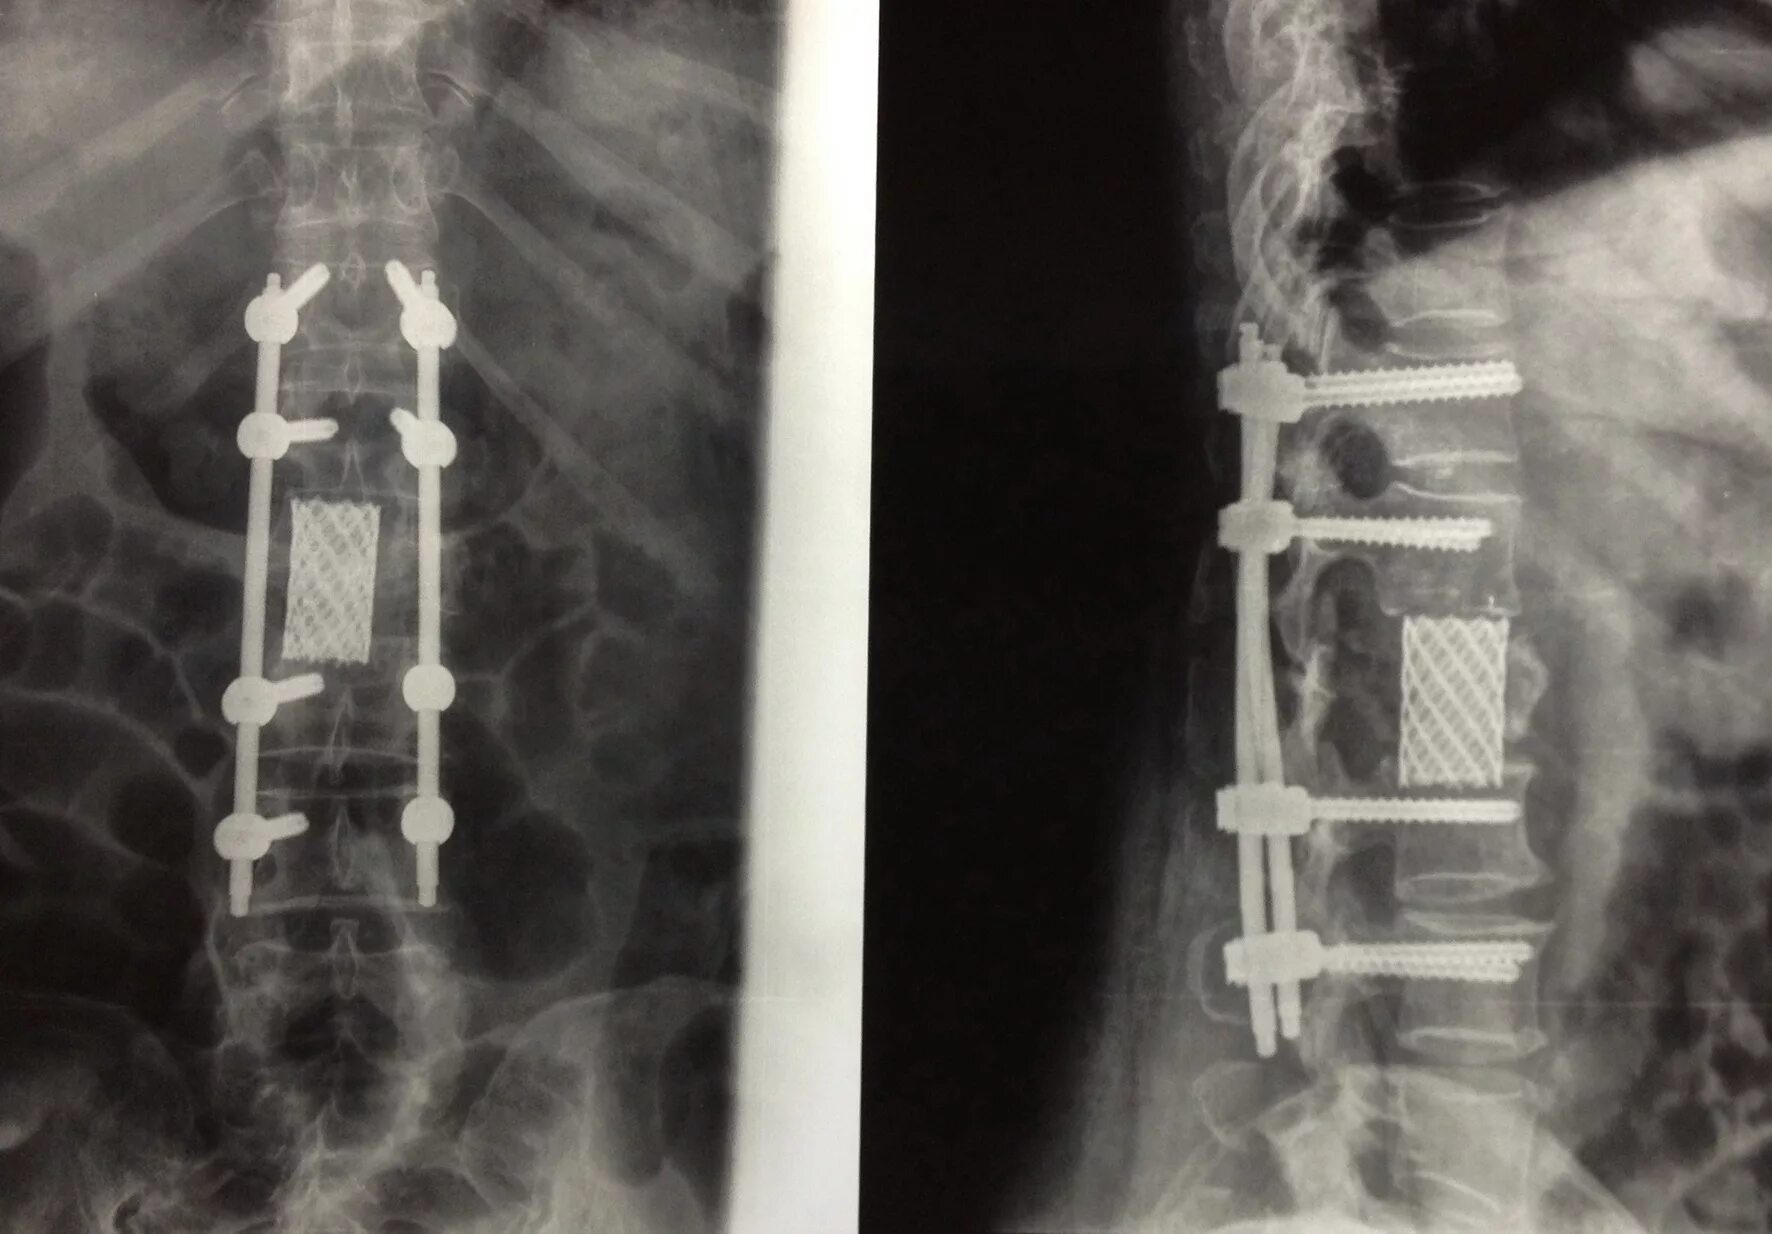

Перелом позвонка инвалидность